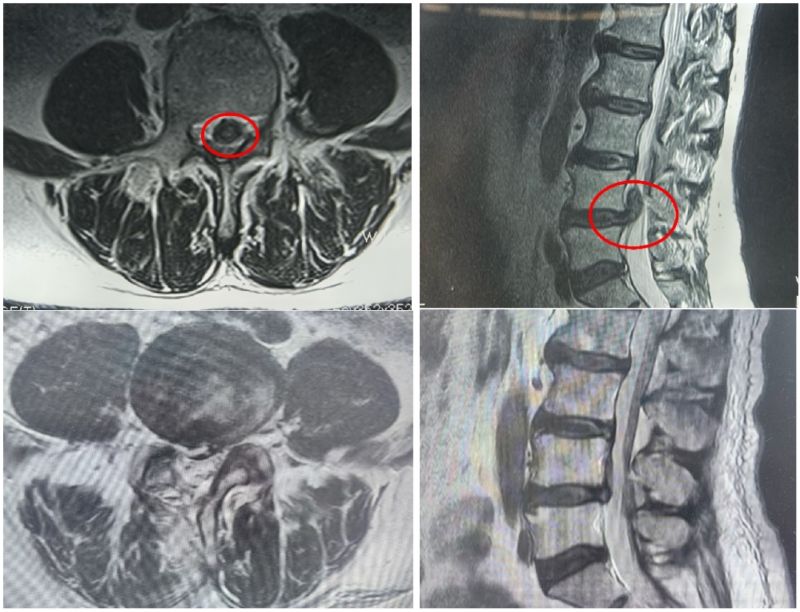

骨科三病區(qū)李鵬主任詳細(xì)詢問病情并查體,結(jié)合腰椎磁共振,診斷為腰椎間盤突出癥伴神經(jīng)根病。詢問病史,患者近1年來飽受疼痛折磨,夜不能寐,到多地醫(yī)院求醫(yī),對開放手術(shù)心生恐懼,一直保守治療。了解病情后,李鵬主任團隊制定了UBE微創(chuàng)手術(shù)治療方案,為患者順利進(jìn)行了單側(cè)雙通道入路內(nèi)鏡下腰4-5椎間盤摘除術(shù)、脊髓神經(jīng)根粘連松解手術(shù)。

術(shù)前、術(shù)后磁共振檢查

患者術(shù)中出血量不到20毫升,僅留下0.8厘米瘢痕。術(shù)后次日楊先生便可下地自由活動,腰腿疼痛感消失,走路也不再一瘸一拐,效果明顯,術(shù)后5天順利出院?;颊呒凹胰藢铢i主任帶領(lǐng)的醫(yī)護團隊表示衷心的感謝。